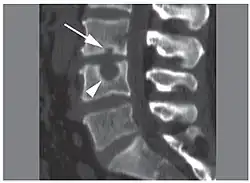

| X-ray image of Schmorl's nodes in the lumbar spine | |

Schmorl's nodes can be detected with X-rays, although they can be imaged better by CT or MRI. They are considered to be vertical disc herniations through the cartilaginous vertebral body endplates. Schmorl's nodes can sometimes be seen radiographically, however they are more often seen on MRI, even when not visible on plain X-rays. They may or may not be symptomatic, and their etiological significance for back pain is controversial. In a study in Spine by Hamanishi, et al., Schmorl's nodes were observed on MRI in 19% of 400 patients with back pain, and in only 9% of an asymptomatic control group. The authors concluded that Schmorl's nodes are areas of "vertical disc herniation" through areas of weakness in the endplate.[4]